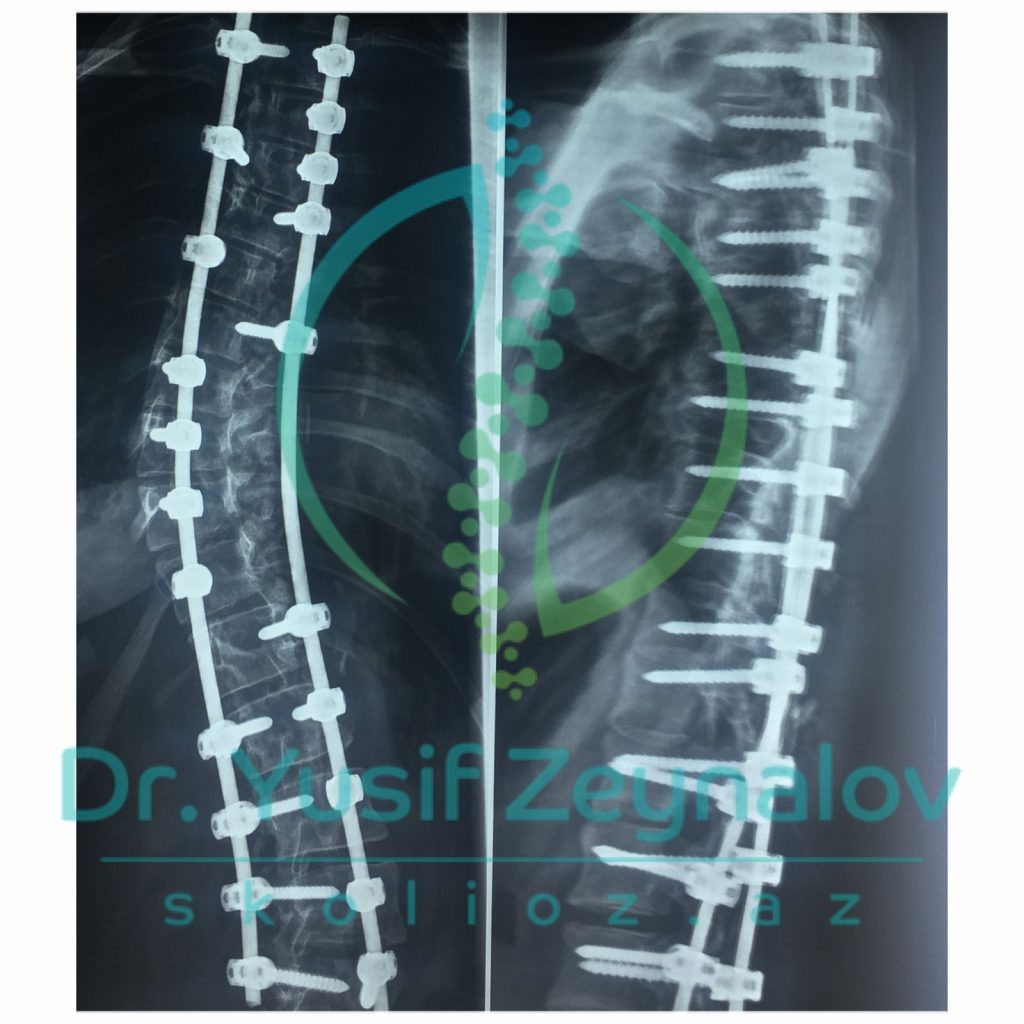

İDİOPATİK SKOLİOZ. COBB BUCAĞI 87°